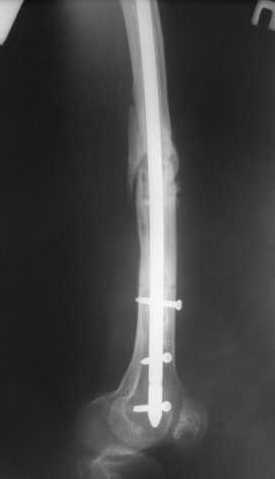

В приложении пример, как их использовали после остеотомии бедра по поводу сросшегося с вальгусом перелома, чтобы не дать гвоздю уйти во внутренний мыщелок.

Да, действительно красивый клинический пример: виден вальгус до операции и последующая коррекция углового смещения на "полярах". Я так понимаю, что в вашей клинике есть возможность использовать различные фиксаторы. Почему не использовали DFN? Спицы какие используете? Киршнера или Илизаровские? С виду очень тонкие...